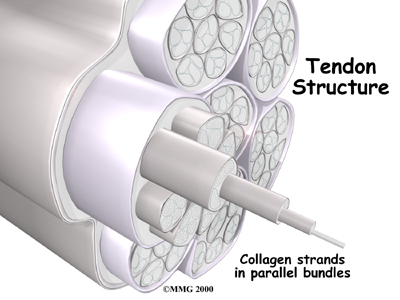

Tendons connect muscle to bone. Tendons are made up of strands of a material called collagen. The collagen strands are lined up in bundles next to each other.

Because the collagen strands in tendons are lined up, tendons have high tensile strength. This means they can withstand high forces that pull against both ends of the tendon. When muscles work, they pull on one end of the tendon. The other end of the tendon pulls on the bone, causing the bone to move.

However, golfer's elbow often is not caused by inflammation. Rather, it is a problem within the cells of the tendon. Doctors call this condition tendonosis. In tendonosis, wear and tear is thought to lead to tissue degeneration. A degenerated tendon usually has an abnormal arrangement of collagen fibers.

Instead of inflammatory cells, the body produces a type of cells called fibroblasts. When this happens, the collagen loses its strength. It becomes fragile and can break or be easily injured. Each time the collagen breaks down, the body responds by forming scar tissue in the tendon. Eventually, the tendon becomes thickened from extra scar tissue.

No one really knows exactly what causes tendonosis. Some doctors think that the forearm tendon develops small tears with too much activity. The tears try to heal, but constant strain and overuse keep re-injuring the tendon. After a while, the tendons stop trying to heal. The scar tissue never has a chance to fully heal, leaving the injured areas weakened and painful.